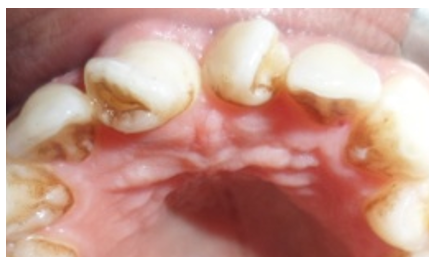

Preprosthetic care and first-generation provisional prosthetic restoration

After rigorous oral hygiene motivation and initial periodontal treatment (scaling, root planing, and polishing), atypical corono-peripheral preparations were performed on the two mesiodens to accommodate ceramic crowns. The preparations adhered to fundamental guidelines, including chamfer or shoulder finish lines with rounded internal angles, rounded edges, and minimal axial taper to prevent undercuts. A mesial stripping of the lateral incisors was also conducted. Endodontic treatment of the mesiodens was performed using a thermal gutta-percha obturation technique (Thermofill) (Figure 4). Two chairside provisional crowns were fabricated using an isomolding technique with self-curing acrylic resin.

Figure 4 Performing two definitive root canal fillings (Thermofill).